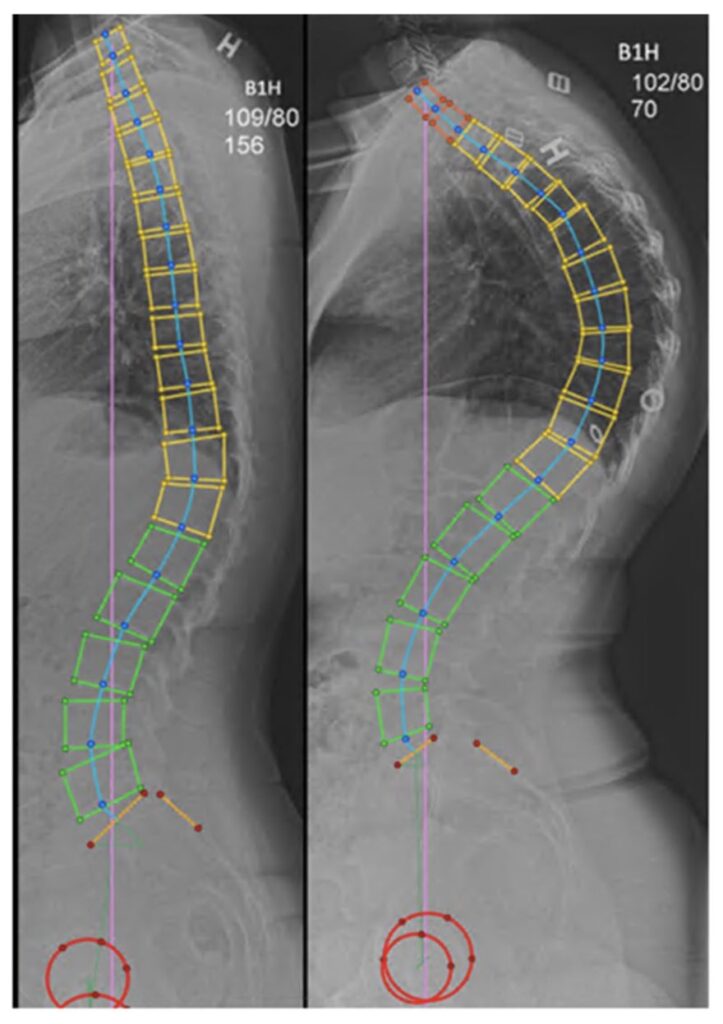

Cifosis de Scheuermann: seguimiento de 39 años desde el diagnóstico en pacientes no operados

Investigar el impacto de la cifosis de Scheuermann (SK) en la calidad de vida relacionada con la salud (CVRS) en pacientes adultos y compararlo con la población general. Además, evaluar si la localización de la cifosis afecta los parámetros pélvicos, la CVRS y la función pulmonar.

Encontramos una menor CVRS en pacientes adultos con SK 39 años después del diagnóstico con respecto a los dominios SRS-22r de dolor y autoimagen, y una tendencia hacia una menor CVRS global en comparación con una población de base. La ubicación del ápice SK no pareció tener un impacto general en la CVRS. No hubo diferencias en los parámetros pélvicos en los dos grupos ni en la función pulmonar.